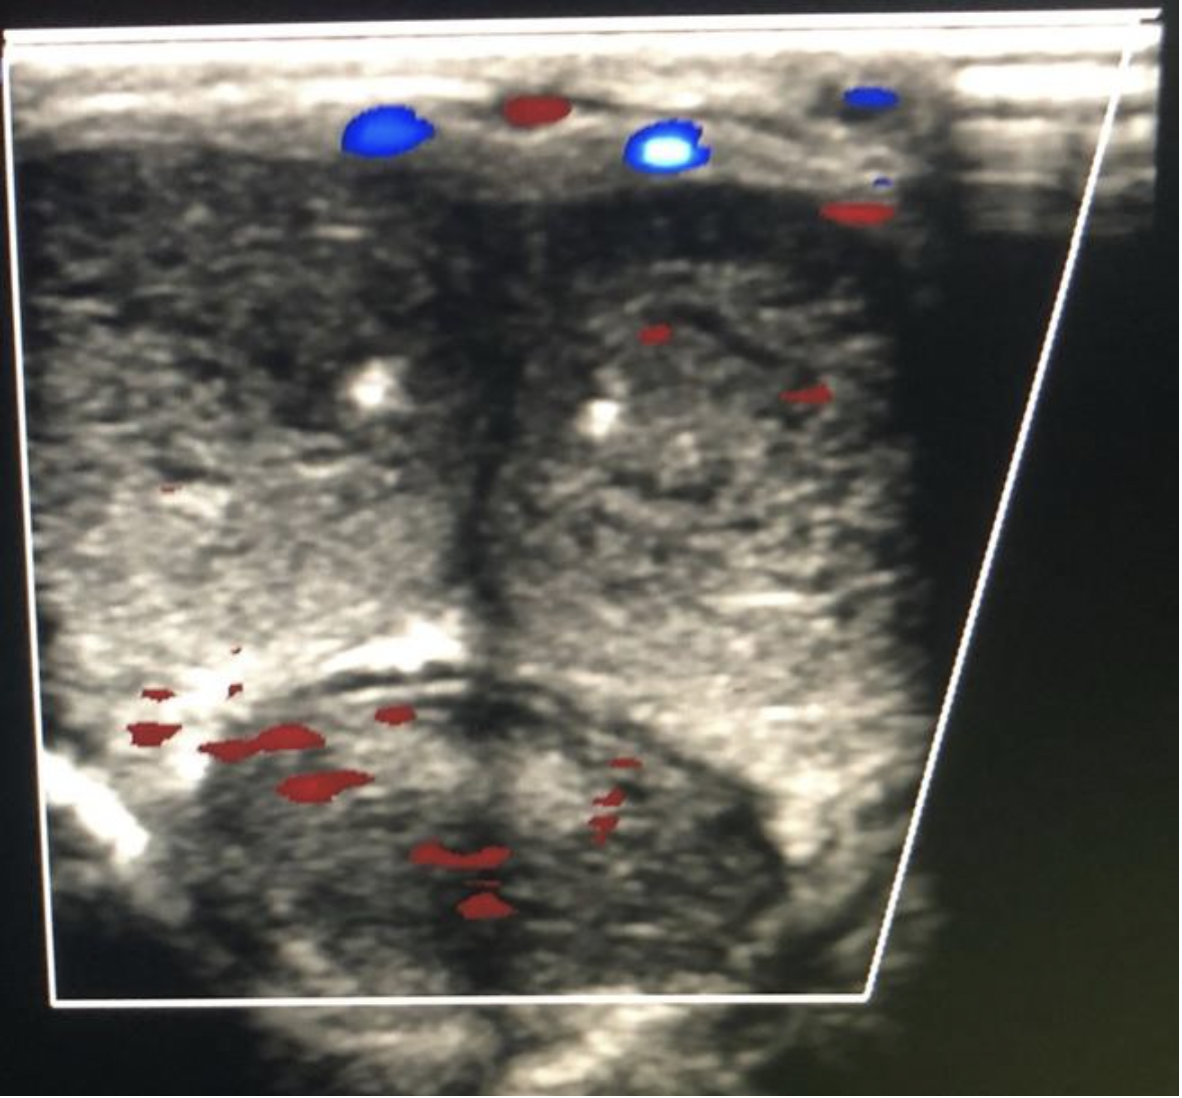

When evaluating a patient with testicular pain:

A. The US system settings should be established while scanning the affected side and remain unchanged when scanning the unaffected side

B. The testicle on the affected side should be scanned first

C. The US system settings should be established while scanning the unaffected side and remain unchanged when scanning the affected side

D. The epididymis on the affected side should be scanned first

When a patient presents with acute scrotal pain,begin the scrotal ultrasound by imaging the unaffected side

The 2D image should be optimized using the normal testicle and then maintain those settings when evaluating the affected side

Use the dual screen function for comparison views for echotexture and perfusion

Scan the affected side with the same settings to look for differences in echotexture and vascularity

Comparison views should also be taken with equipment settings optimized for the UNAFFECTED side